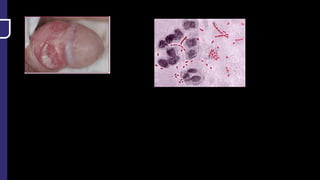

Q. A farmer from UP came to the OPD with ulcerating nodules on hand with pus

discharge from the same. It slowly progressing and worsening. On examination regional

lymphadenopathy is seen. The doctor ordered HPE with below finding .

Diagnosis is?

a. Fish tank granuloma

b. Leishmaniasis

c. Sporotrichosis

d. Sarcoidosis

Q. A farmerfrom UP came to the OPD with ulcerating nodules on hand with pus discharge from the same. It slowly progressing and worsening. On examination regional lymphadenopathy is seen. The doctor ordered HPE with below finding . Diagnosis is? a. Fish tank granuloma b. Leishmaniasis c. Sporotrichosis d. Sarcoidosis